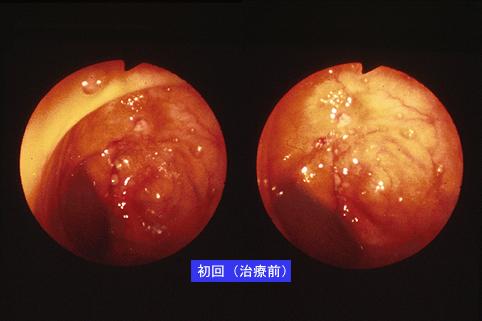

疾病(病理主体)的分类炎症性・溃疡性疾患/结核

部位(按器官分)大肠/降结肠

检查方法内窥镜